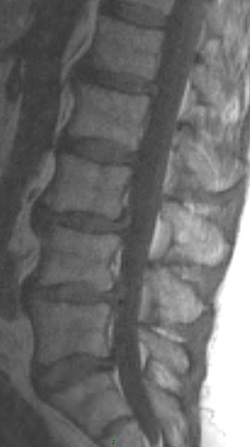

1. Aside from disc changes and spondylosis, what additional finding is present.

2. What are the types of spondylolisthesis? Pertaining to the anterolisthesis, which type does the patient have?

3. What is the appropriate way to asses stability?